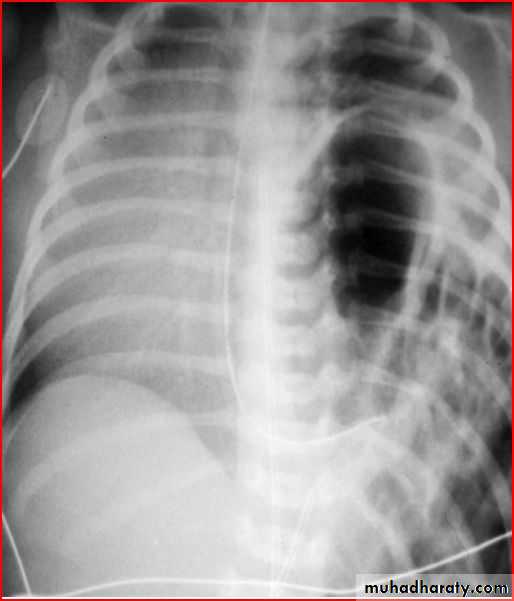

Diaphragmatic hernia

Rt. Diaphragmatic hernia or diaphragmatic eventration

Rx >> endotracheal tube and o2 and NG tubeDiaphramatic hernea and endotracheal tube

Rt. Diaphragmatic hernia (rare) + pneumothorax in lt. due to lung hypoplasia